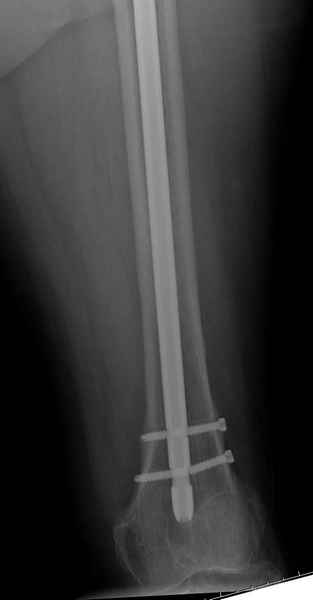

77 летняя больная направлена в нашу клинику на дальнейшее лечение.

Из истории, травму получила в сентябре 2007 года и по поводу перелома шейки бедра больная была проперирована тремя каннюлированными шурупами с явным нарушением технологии установки шурупов. Внизу вместо одного шурупа имеется два, что привело к стрессу латерального кортекса.<br>

Через месяц по поводу ятрогенного подвертельного перелома сделана фиксация длинной Гамма 3. <br>Установлен без проксимальной блокировки? (set screw).<br>

В данный момент имеется несостоятельность конструкции и ложный сустав.<br>

Передвигается с помошью костылей, конечность укорочена на 2 см.<br>